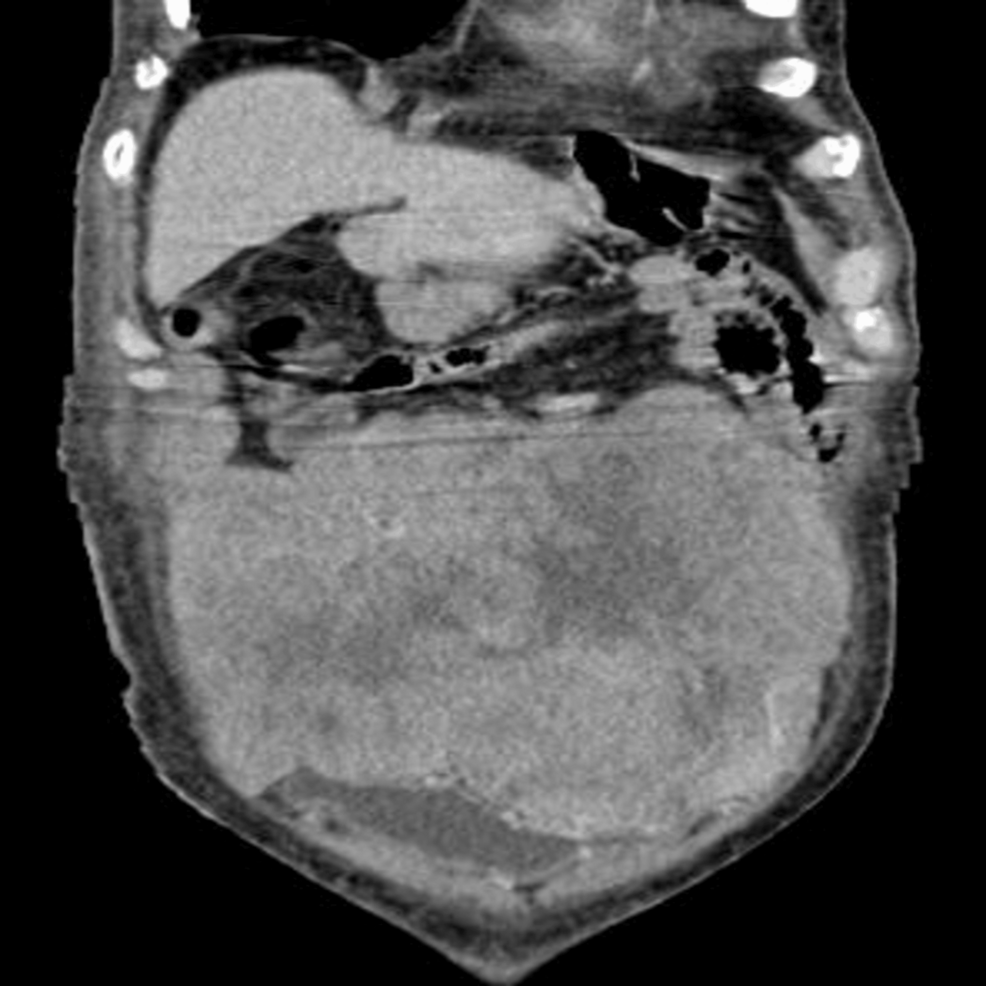

- ectopic IGF-2 Production: The most common cause is a tumor producing IGF-2, often located in the liver, lungs, or other organs. Imaging studies (CT scans, MRI) are essential to identify such tumors.

In our patient, extensive imaging revealed a small, previously undetected hepatocellular adenoma (a benign liver tumor) expressing high levels of IGF-2. This was confirmed through biopsy and immunohistochemical staining. This diagnosis falls under the umbrella of adult-onset hypoglycemia and requires specialized care.

- Imaging Studies: Perform a CT scan or MRI of the abdomen and chest to identify potential tumors.